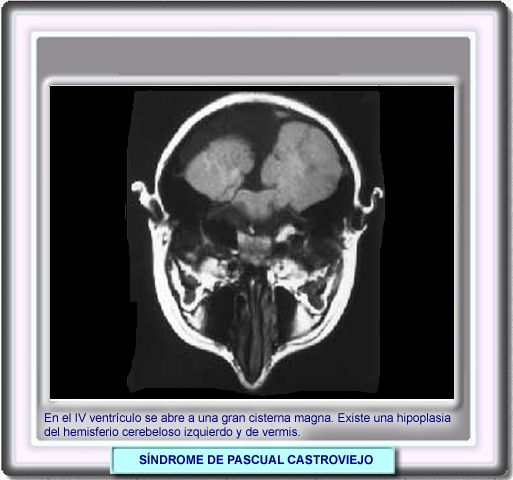

Síndrome de Pascual Castroviejo

Las malformaciones vasculares más características son la hipoplasia de troncos supraaórticos (habitualmente de carótida o vertebral ipsilateral al hemangioma) y la persistencia de arterias embrionarias intracraneales o extracraneales (arteria trigeminal) o la coartación de aorta. La presencia de cardiopatía congénita, aunque menos frecuente, también forma parte de las alteraciones consustanciales del síndrome. Las pacientes tienen además un retraso psicomotor leve-moderado. El grado de hipoplasia cerebelosa es variable, desde defectos parciales a una agenesia global asociada a una malformación tipo Dandy-Walker.